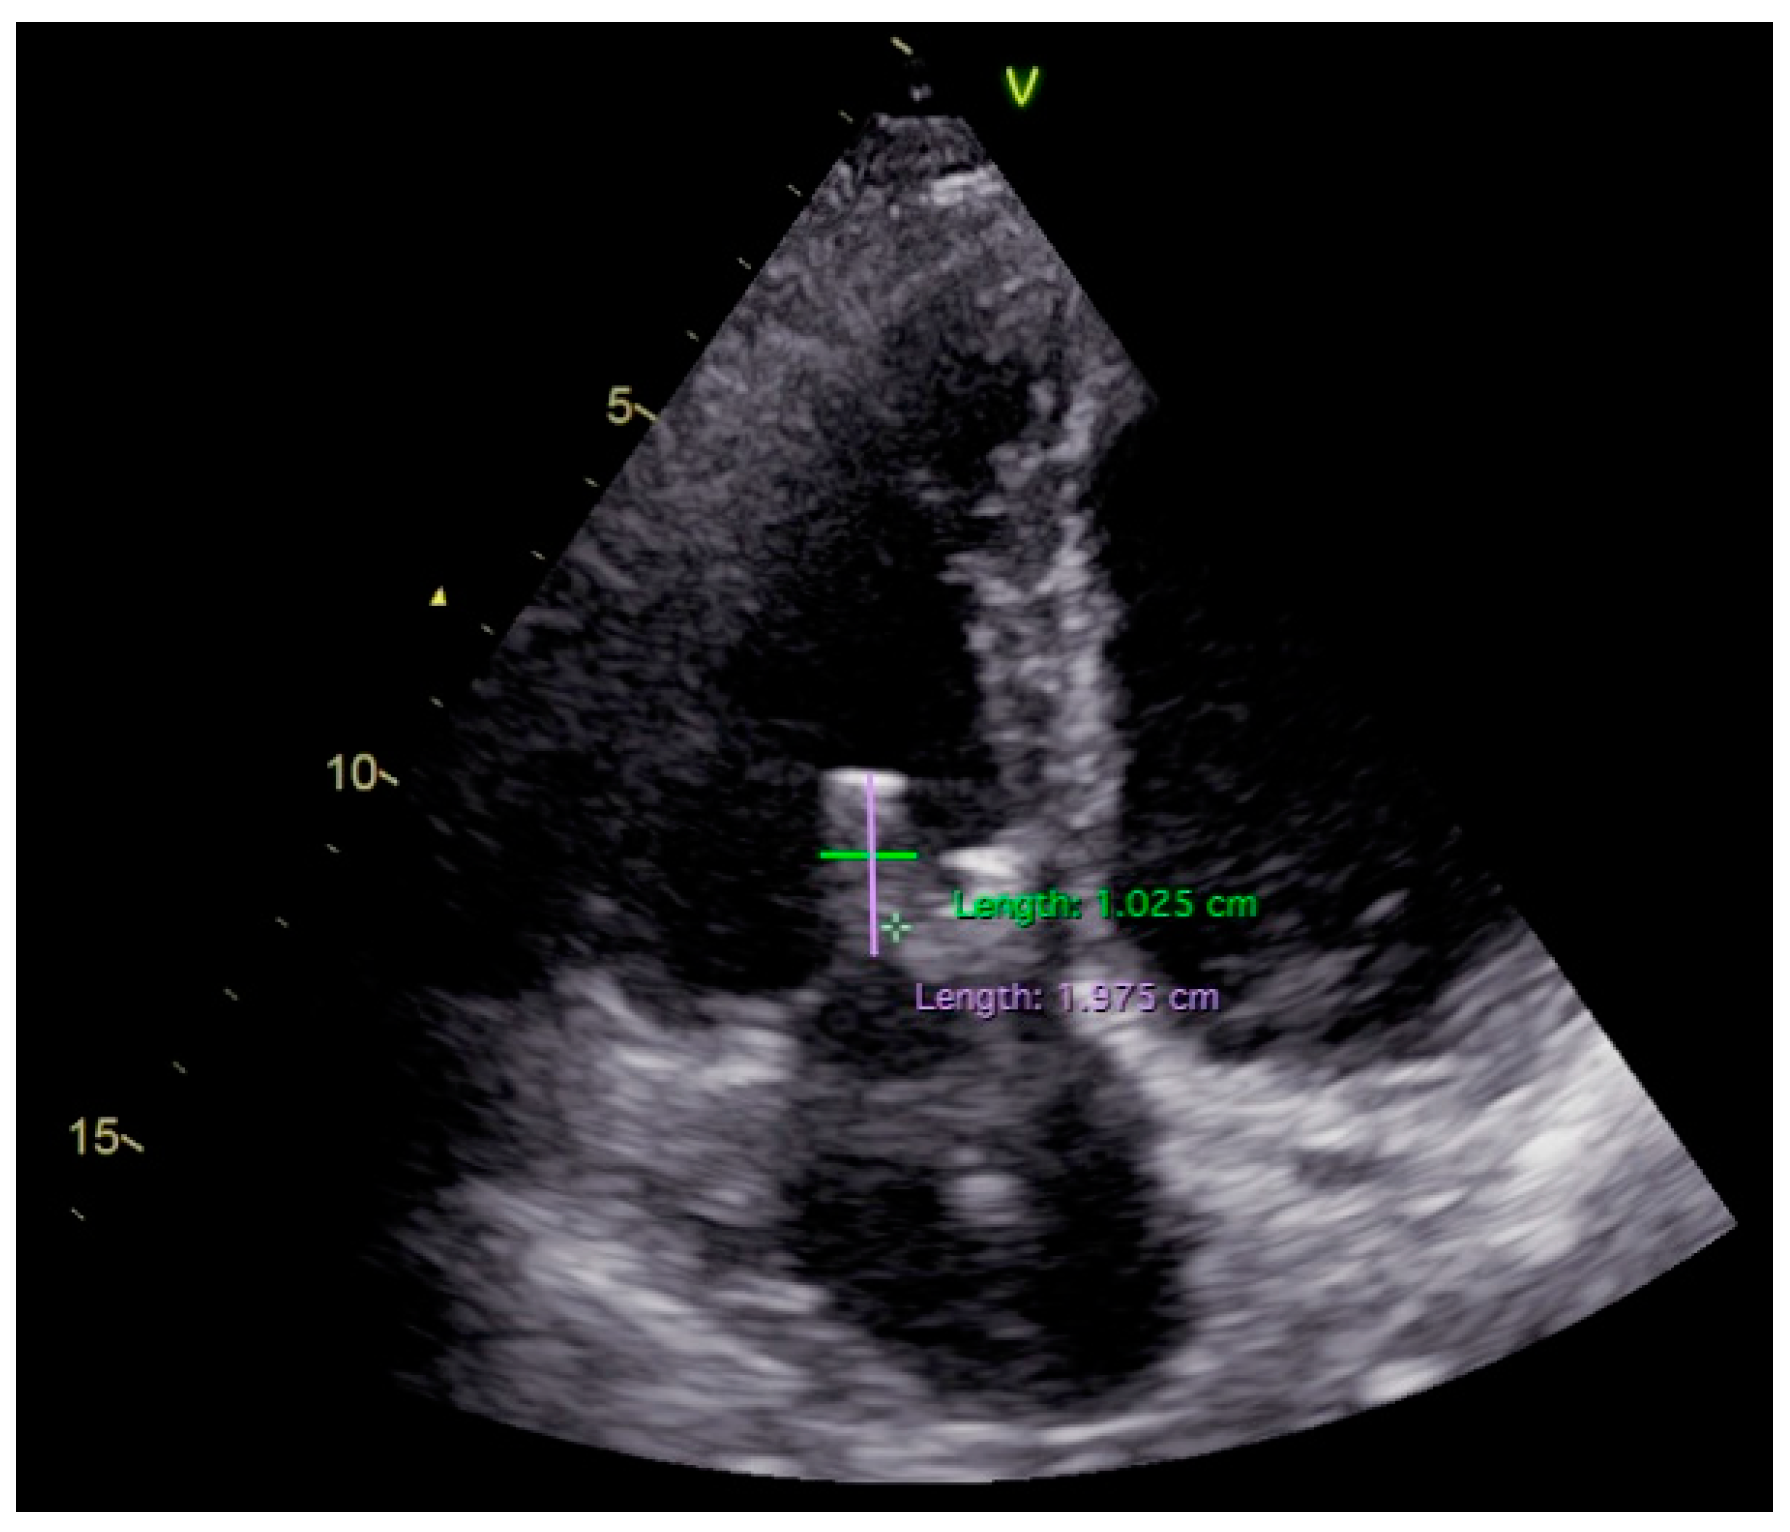

2. Case Report